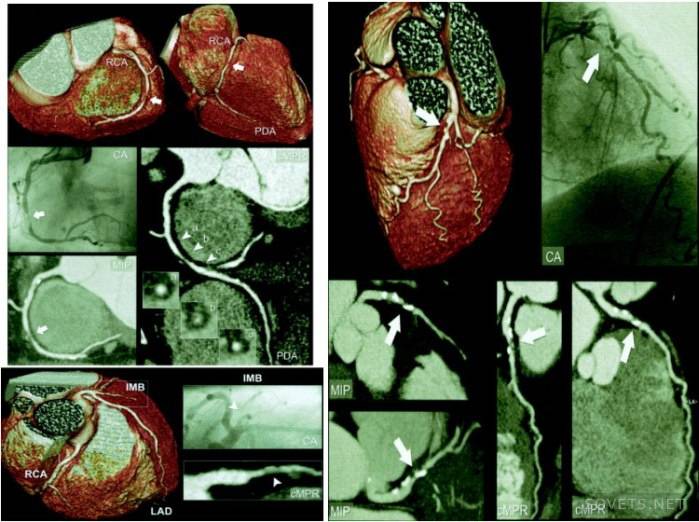

- Obtendo imagens espaciais 3D mais precisas. Modelos tridimensionais mostram com mais precisão a natureza e a localização da patologia. O uso de técnicas de escaneamento em espiral permitiu o uso da angiografia, ou seja, estudo das artérias, para identificar aneurismas vasculares, estreitamento, seu comprimento.

Tomografia computadorizada do tórax revela doenças do coração, pulmões, artérias coronárias, esôfago, laringe, grandes vasos sanguíneos. Com sua ajuda, tuberculose, aneurismas da aorta e tumores são detectados. 4 horas antes do procedimento, não é recomendado comer alimentos. É assim que a foto do coração tirada durante o exame parece.